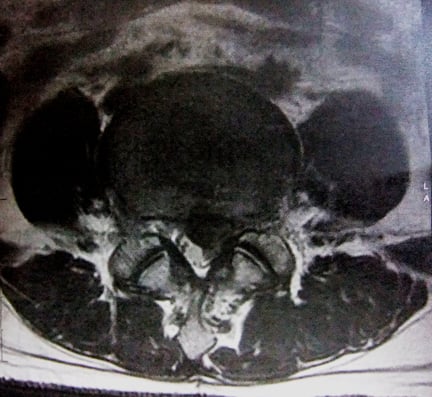

椎間板ヘルニア

診断名:椎間板ヘルニア

現在、左臀部に鈍痛があり、左下腿外側には強い放散痛(L4・L5神経領域)を訴えています。安静時の痛みはありませんが、夜間痛を伴います。